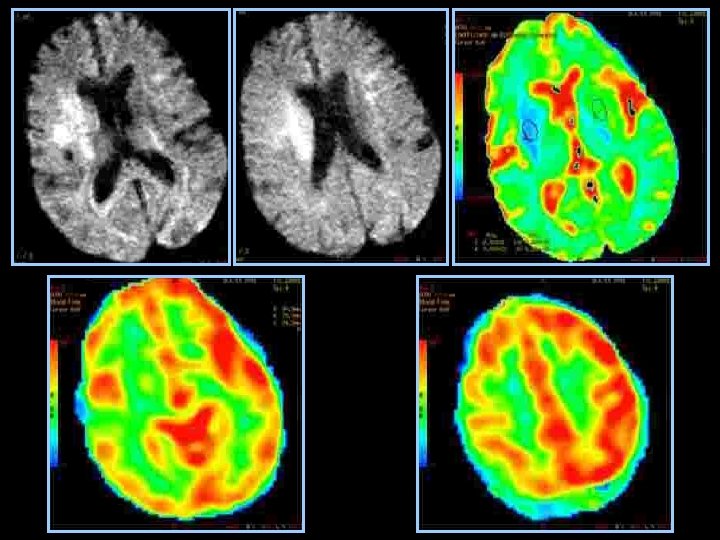

VALEUR PREDICTIVE du CBF • CBF >55% : récupérable > 6 heures • CBF > 35%: récupérable < 6 heures • CBF< 35% : Résultats ? Risques d’hémorragie Ueda, J Cereb Blood Flow Metab 1999, 19, 99 -108

CBF CBV MTT

Sélection des patients • Être efficace : y a t’il du parenchyme a sauver ? – Diffusion : nécrose définitive! discutable: • diminution des zones d’anomalies de diffusion après thrombolyse IA • Hétérogénéité des niveaux de baisse d’ADC à l’intérieur de la zone anormale • diminution progressive de l’ADC de la périphérie vers le centre: notion de seuil? – < 50 % : évolution vers la nécrose certaine – >70 -80% : récupérable si recanalisation – Importance de l’évaluation de l’ischémie: • collatéralité en angiographie • perfusion en IRM ou en scanner

Sélection des patients • Ne pas être dangereux: identifier les patients à haut risque d’hémorragie – Localisation profonde – Délai – Baisse de l’ADC: risques si ADC< 33% – Hypoperfusion sévère : CBF< 33%